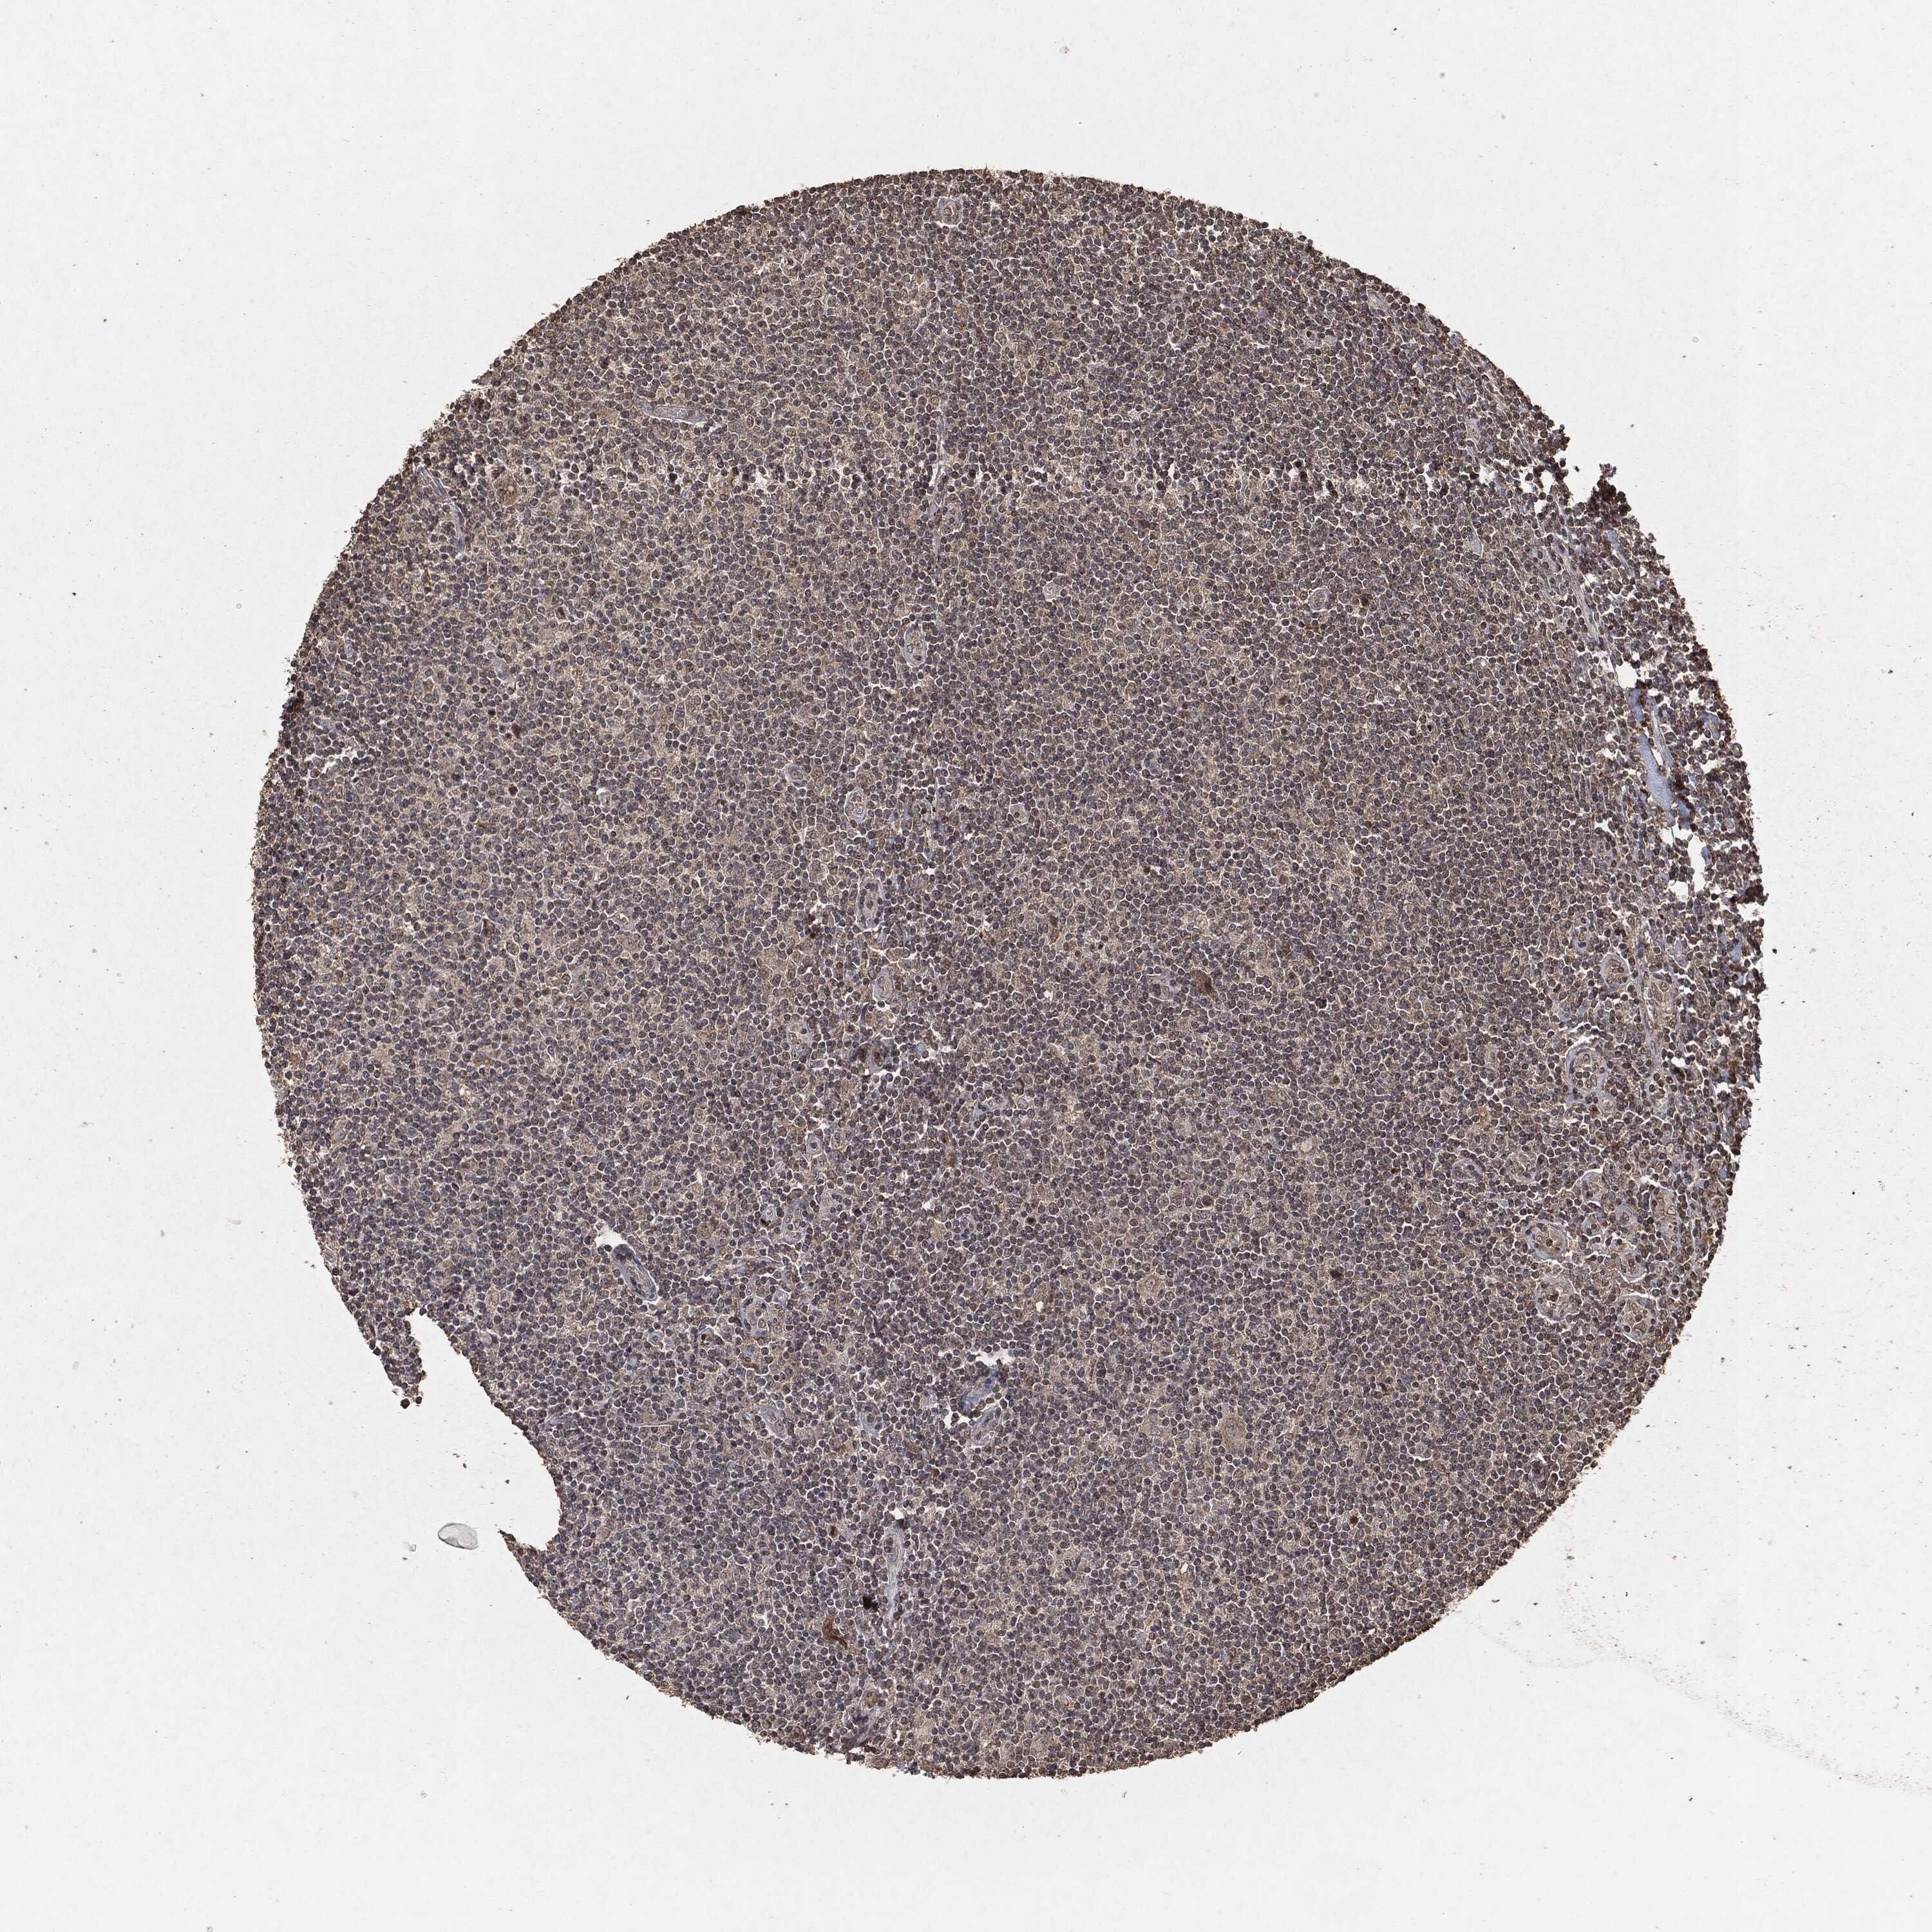

CANCER LYMPHOMA Show tissue menu

LYMPHOMA - Protein expressioni

A mouse-over function shows sample information and annotation data. Click on an image to view it in a full screen mode. Samples can be filtered based on level of antibody staining by selecting one or several of the following categories: high, medium, low and not detected. The assay and annotation is described here.

Each image is clickable and will lead to virtual microscopy that enables deeper exploration of all samples and also displays staining intensity scores, fraction scores and subcellular localization as well as patient and tissue information for each sample.

Malignant lymphoma, non-Hodgkin's type, High grade

Hodgkin's disease, NOS

Malignant lymphoma, non-Hodgkin's type, Low grade